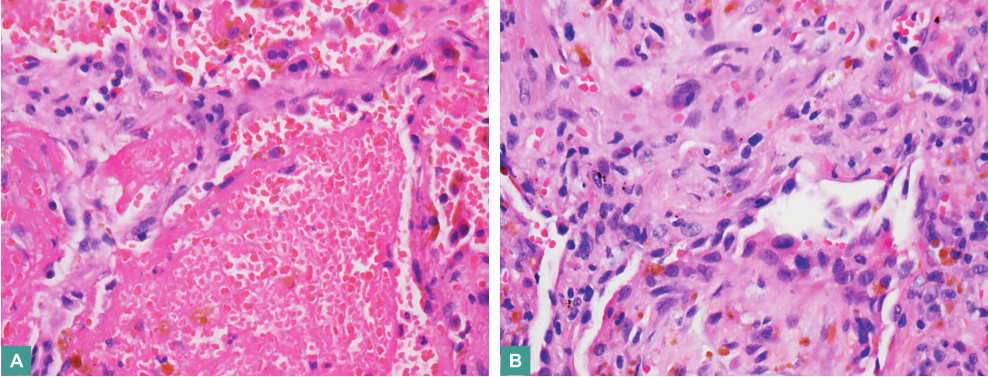

口服泼尼松23天后,患者咯血症状无改善,自行停药。停药1个月后复查胸部CT,提示双肺病灶较前增多、增浓(图2)。转胸外科行胸腔镜下肺活检,病理结果示:病灶边缘腺泡腔内肿瘤组织呈充填式生长,病灶中央见不规则互相吻合、沟通血管腔隙,内皮被覆异型内皮细胞(图3)。术后病理诊断:肺血管肉瘤。由于患者发病后多次查体,未见皮肤、乳腺异常,无骨骼疼痛,心脏彩超、全腹彩超皆未发现血管性肿瘤征象,故判断肺部病灶为原发。

图3 肺活检病理结果

病灶边缘腺泡腔内肿瘤组织呈充填式生长(A. HE染色,×200);病灶中央见不规则的互相吻合、沟通的血管腔隙,内皮被覆异型内皮细胞(B. HE染色,×200)

肺血管肉瘤多为转移性,原发性罕见,诊断时需排除肺外原发病灶。肺血管肉瘤的临床表现无特异性,以咯血最常见,其次为咳嗽、呼吸困难、胸痛等,肺部无特异阳性体征。影像学表现可为肺内孤立性肿块、多发结节、胸腔积液、气胸,其中以双肺多发混合密度结节影常见,病灶中央密度高,边缘可出现晕轮征,结节直径多<3cm。支气管镜检查可见腔内血迹,少见异常病灶。肺血管肉瘤的诊断依赖组织病理学结果。显微镜下见瘤组织由不规则的互相吻合、沟通的血管腔隙构成,内皮被覆异型内皮细胞,呈梭形、立方形或不规则形。肿瘤细胞异型性与其分化程度相关。分化程度高者血管腔明显,瘤细胞异型程度轻,核分裂象少;分化程度差者内皮细胞呈实巢状,弥漫性排列,血管腔不明显,内皮细胞异型性明显,分裂象多见,肿瘤组织内常见坏死征象。免疫组化对于一些复杂病例的诊断及鉴别诊断具有重要作用。血管肉瘤细胞常表达CD31、CD34等血管来源肿瘤的特异性标志物,其中以CD31特异性最强,不表达CK、TTF-1等上皮性标志物。诊断肺血管肉瘤时,需注意与肺转移癌、肺低分化腺癌、肺上皮样血管肉瘤、肺淋巴瘤、恶性黑色素瘤及肺感染性疾病、肺血管炎性疾病等相鉴别。